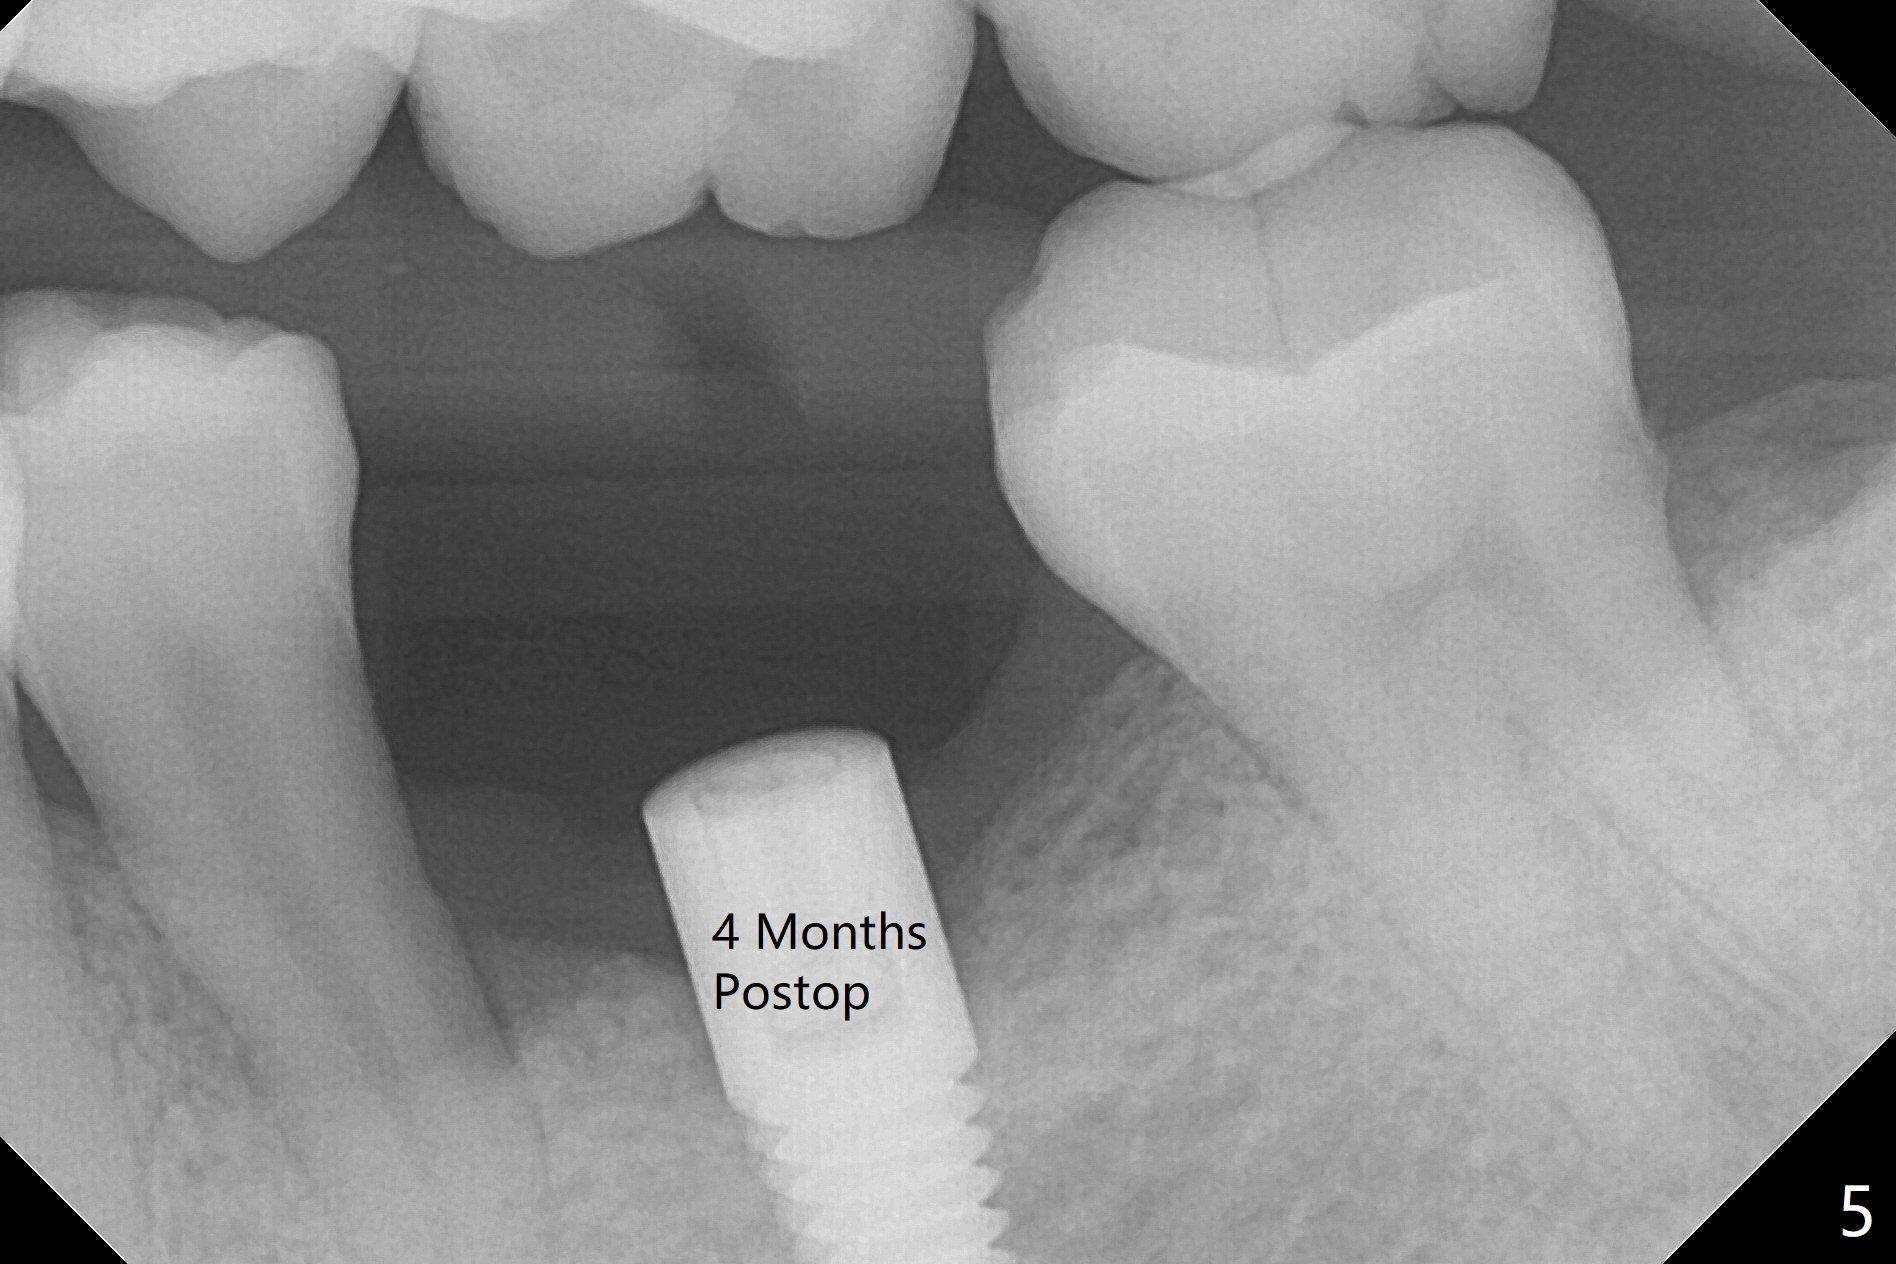

After 4x11.5 mm drill with 10.5 mm offset for bone-level implant at #19, a 4.5x14 mm tissue-level tapered tap is used with high torque. The same sized implant is placed in-completely with apical space (Fig.1 ^). Following reuse of the guide and 4.5x7.3 mm drill, the implant is placed deeper easily (Fig.2-4). The implant threads are subcrestal buccally (B (L: lingual plate), as compared to design in Fig.3'). Later the implant is placed a little deeper with insertion torque of 25 Ncm. There is no crestal bone loss 4 months postop (Fig.5). Waterlase is used for gingivectomy without anesthesia or burn after placing a 4x5 mm abutment. The access is difficult due to severe bone loss. There is no gap between the implant threads (osteointegration) 9 months postop/immediate post cementation (Fig.6 < (coronavirus)), although the crestal bone has lost. After cementation, the tooth #20 has no mobility; note bone loss around the root of #20 (Fig.5). In spite of the residual cement, there appears no bone loss 2 months postop (Fig.7). Instead the distal crestal bone is more organized.